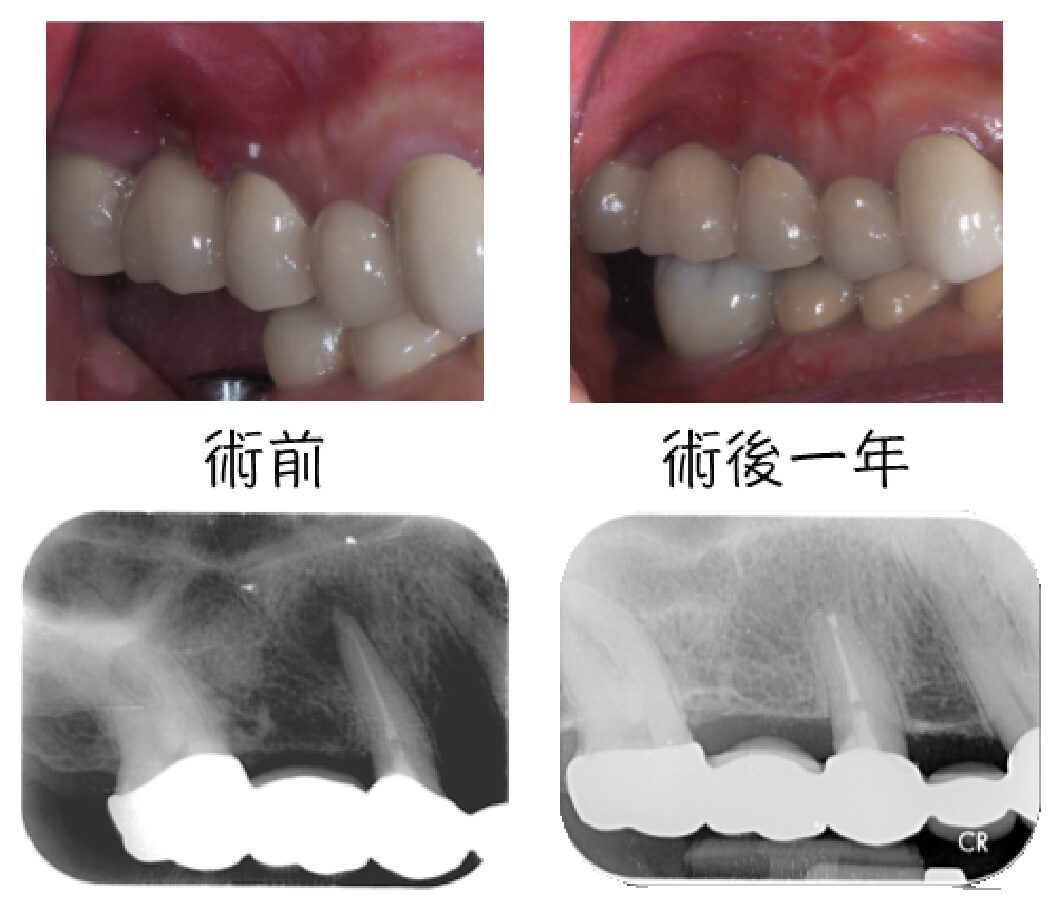

左圖中第一大臼齒兩個牙根皆因為根管內的感染造成根尖周圍炎(紅線中黑黑的地方),在根管治療後追蹤一年可發現骨頭都已經恢復正常的樣子

手術結束後一年可見根尖周圍炎的狀況恢復良好,膿包也都沒復發,病人也無需更換舊有假牙。